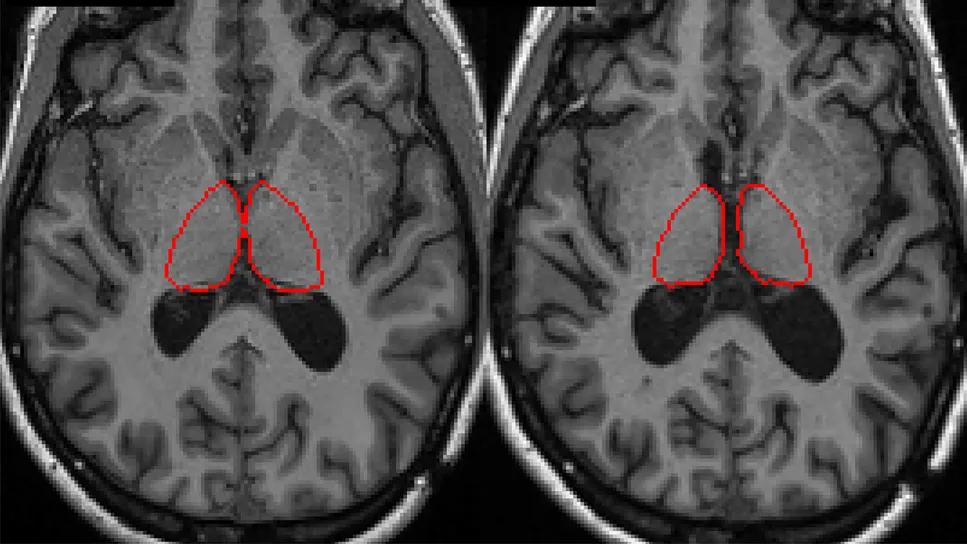

Longitudinal brain MRIs demonstrating thalamic atrophy (red-circled regions) over a six-year period. Image courtesy of the Kunio Nakamura lab, Cleveland Clinic.

Thalamic atrophy is significantly associated with unique neuropsychological testing (NPT) profiles in people with multiple sclerosis (MS), independent of other regional brain quantitative measures. So finds a new study by Cleveland Clinic researchers that leveraged machine learning to link cognitive impairment and neuroimaging biomarkers in MS.

The researchers identified two clusters based on PC1, one of which had a significantly greater degree of thalamic atrophy in both the training and validation cohorts and similar rates of change in the other measured quantitative MRI metrics. Significant correlation was found between PC1 and the thalamic atrophy rate, with higher standardized cognitive scores associated with lower rates of atrophy.